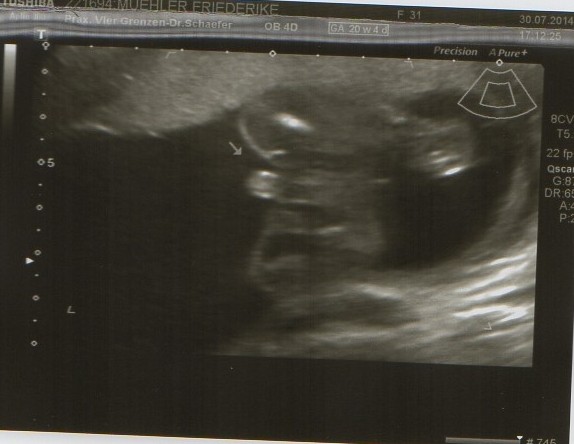

Heute gab es ein Fotoshooting der besonderen Art beim Opa auf Arbeit. Sein Kollege, der stellvertretende Chefarzt der Kinderklinik und gleichzeitig Guru des Ultraschalls, hatte sich bereit erklärt den werdenden Eltern noch ein paar aktuelle Fotos zu machen. Leider gab es kein 3D, aber dafür ein paar süße Fotos und vor allem Videos unseres Sohnemannes, der sich die ganze Zeit über ruhig verhielt und sich der Kamera, äh dem Schallkopf stellte.